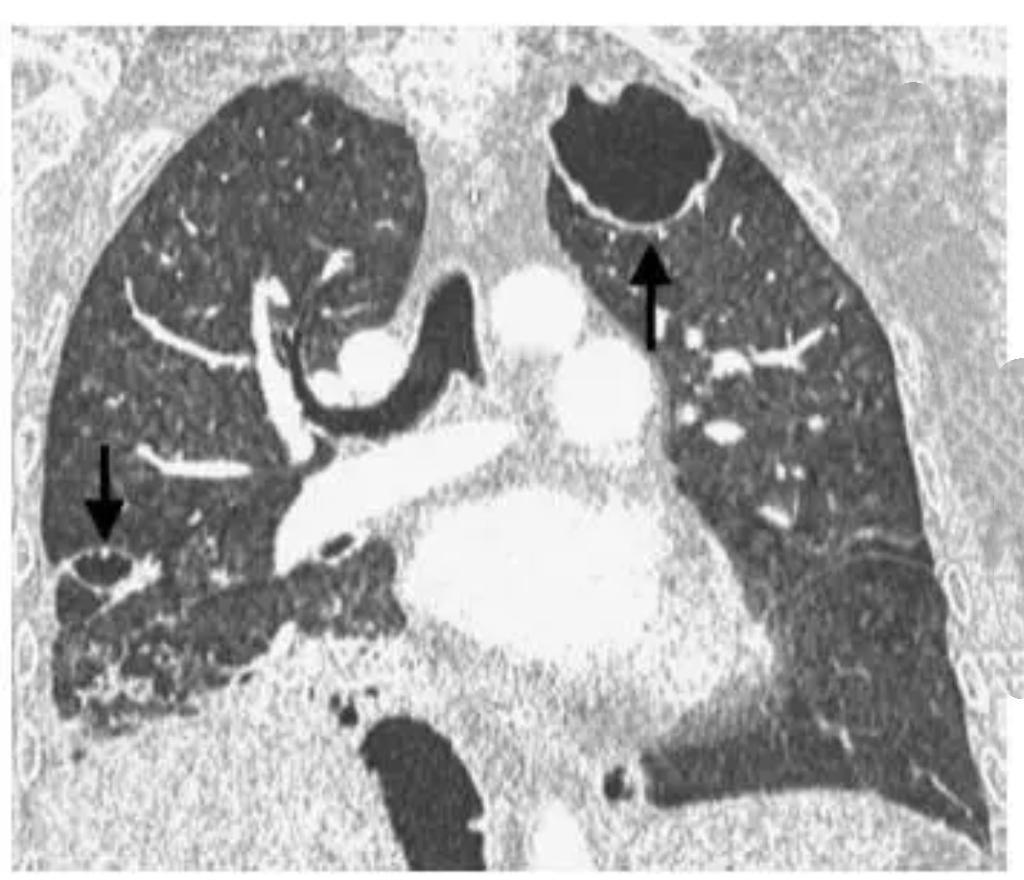

20岁男生小李长期熬夜、饮食不规律,免疫力下降,竟被结核杆菌“盯上”,肺部被“啃”出10多个空洞,咳嗽、发热、咯血等症状频发。所幸及时就医,经规范抗结核治疗,病情逐渐好转。提醒年轻人,务必重视健康,规律作息。